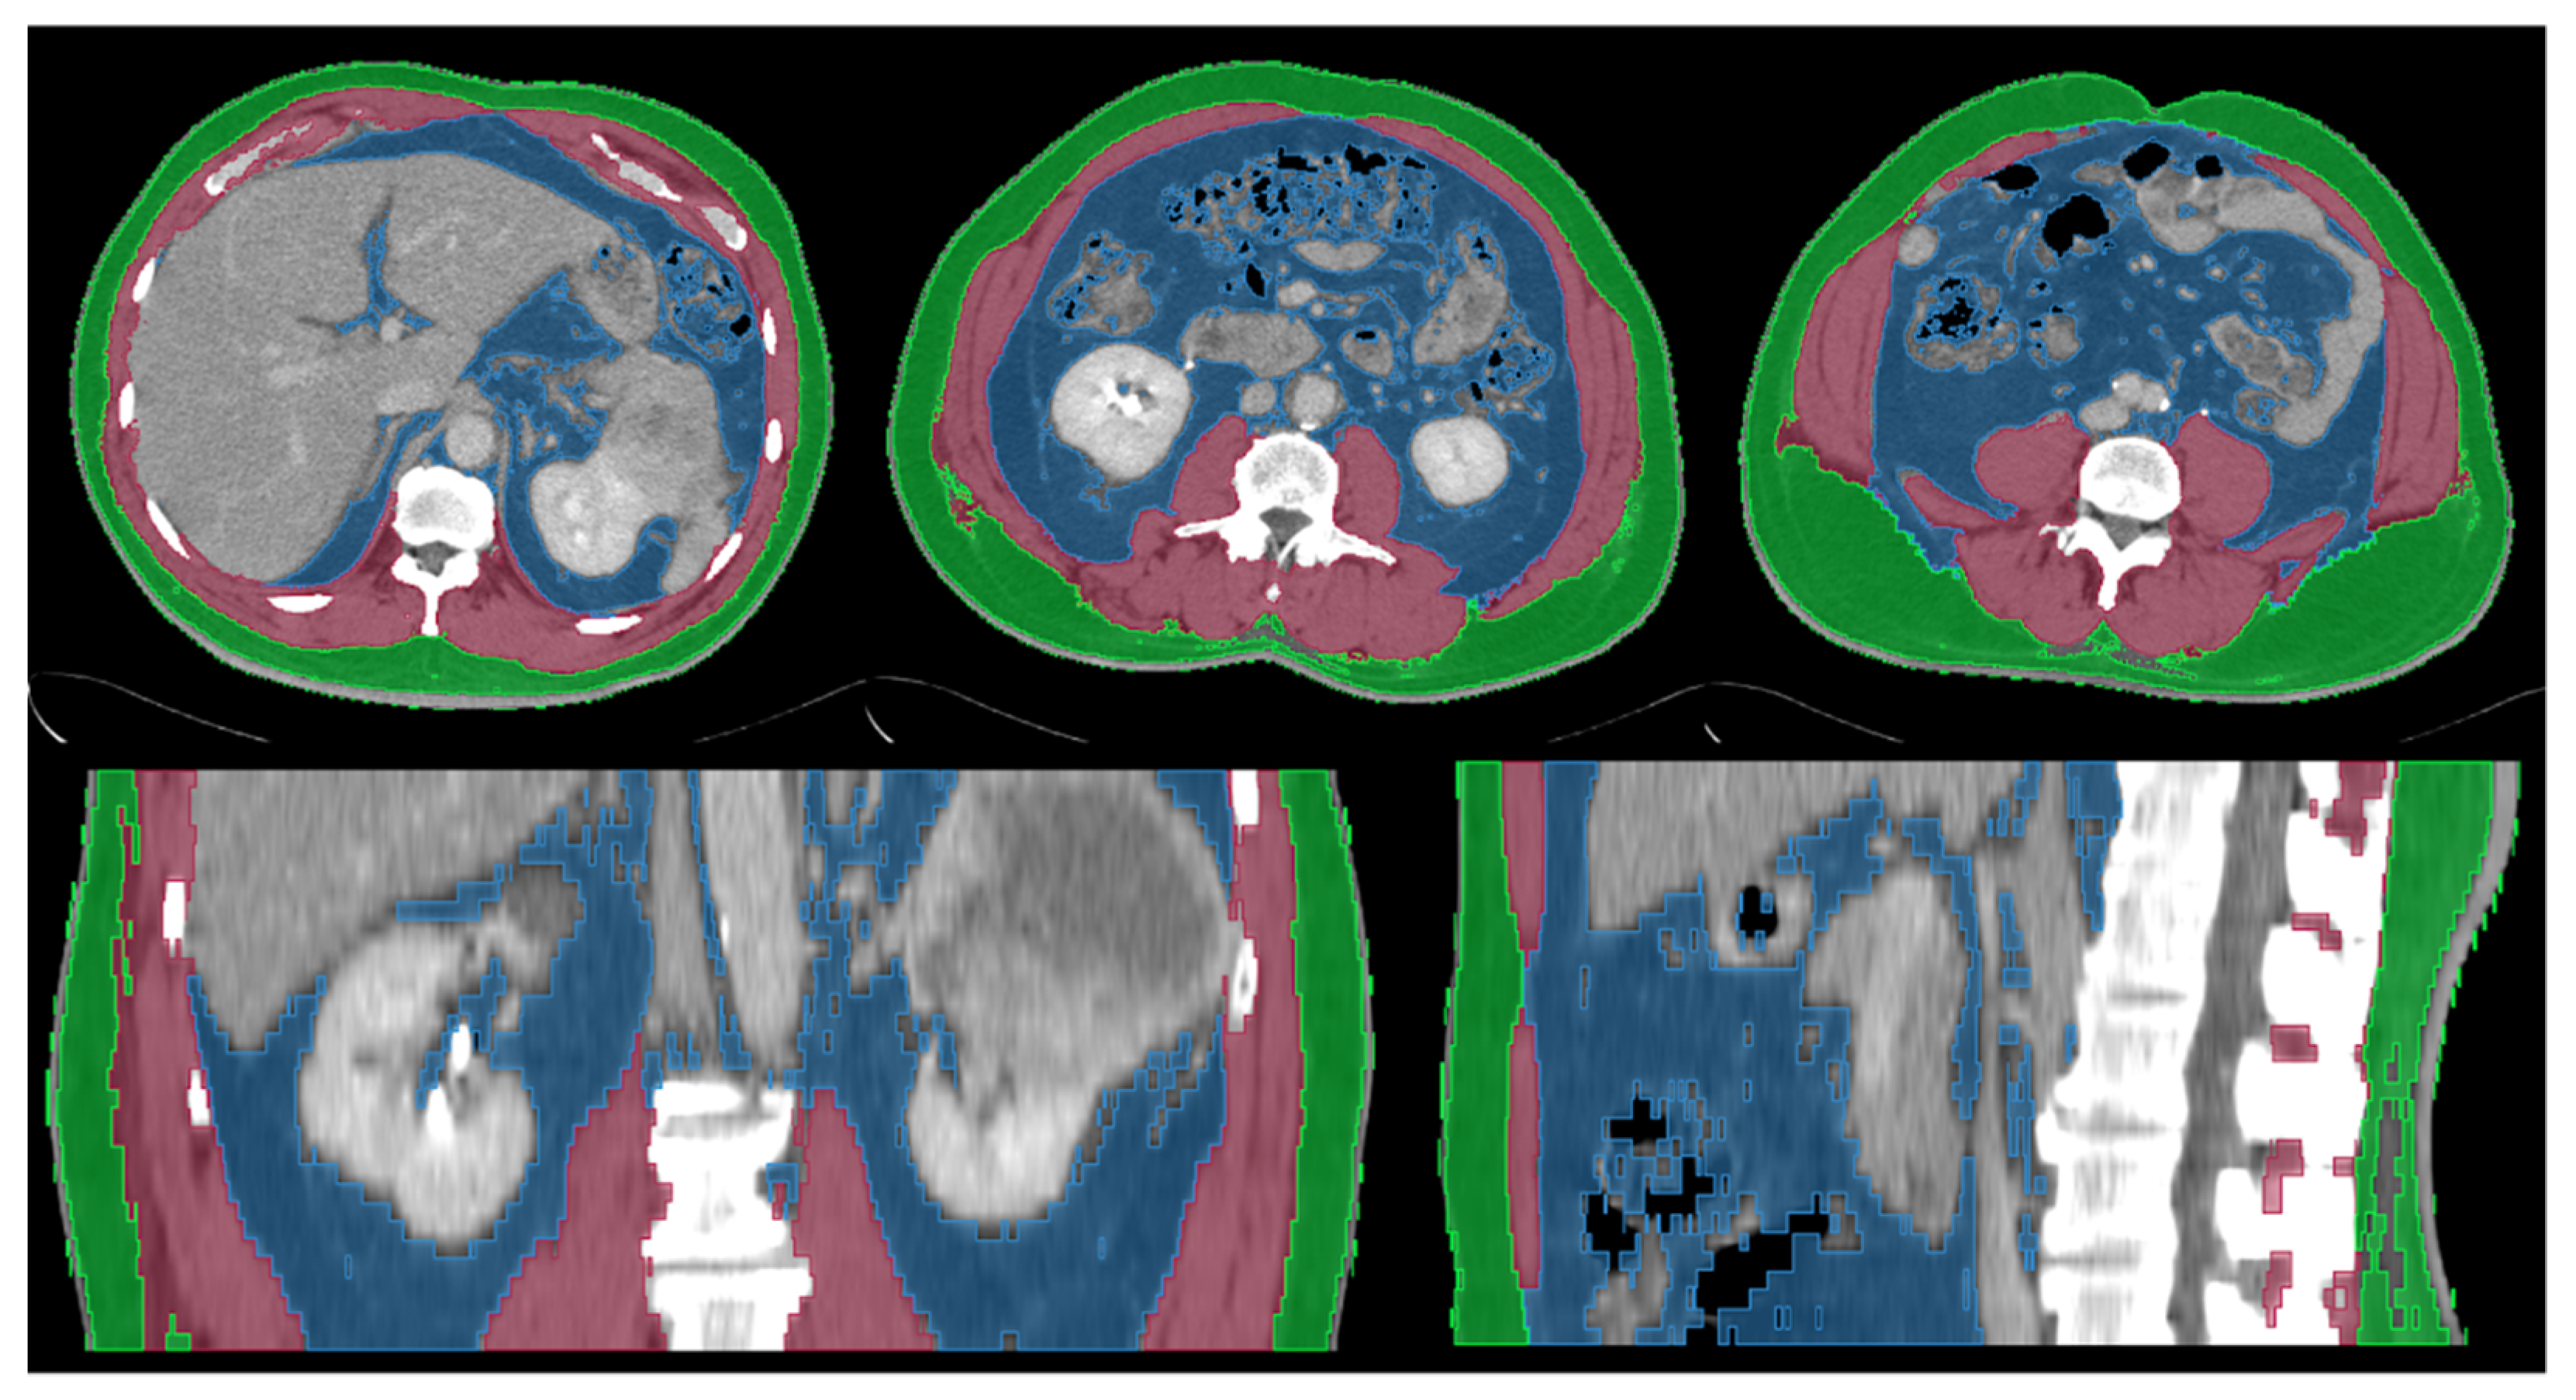

Body composition variables were measured based on the CT images for cancer staging. Abdominal computed tomography (CT) scans were performed with and without intravenous contrast before surgery as routine. The slice thickness and interval ranged from 3 to 10 mm with a median of 5 mm. Body composition analysis was performed using 3D Slicer (www.slicer.org, accessed on 1 January 2015 [14]) using a semiautomatic segmentation method. Abdominal CT images were segmented into three components: skeletal muscle tissue (SMT), subcutaneous adipose tissue (SAT), and visceral adipose tissue (VAT). The CT attenuation value of adipose tissue was defined as −190 to −30 Hounsfield units (HUs) [15]. Three-dimensional (3D) volumes at the level of the costophrenic angle to the iliac crest and two-dimensional (2D) cross-section areas at the level of the third lumbar spine (L3) showing both transversal processes were calculated for SMT, SAT, and VAT. Figure 1 shows an example of body composition analysis on abdominal CT images.

Figure 1.

Example of abdominal computed tomography body composition analysis (upper left: axial plane at the level of costophrenic angle, upper middle: axial plane at the level of L3, upper right: axial plane at the level of iliac crest, lower left: coronal plane, lower right: sagittal plane). Skeletal muscles tissue (red area), subcutaneous adipose tissue (green area), and visceral adipose tissue (blue area) were segmented. Three-dimensional (3D) volumes from the level of costophrenic angle to iliac crest and two-dimensional (2D) cross-section areas at the level of L3 were calculated.